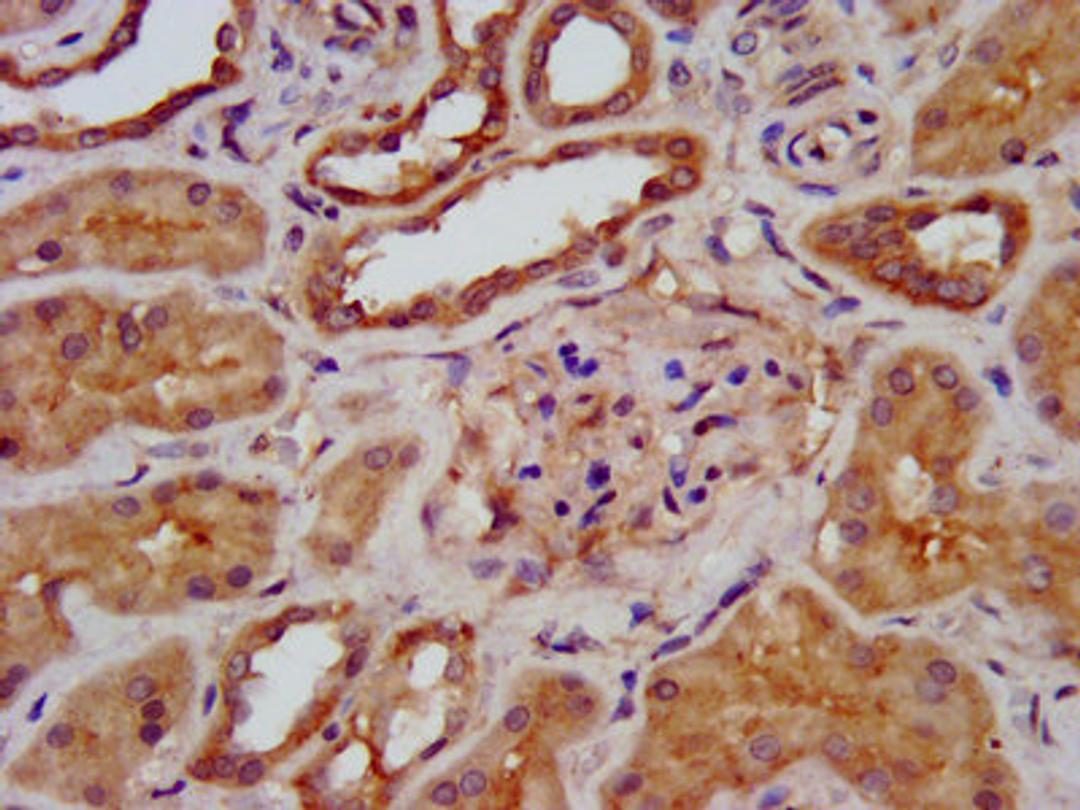

IHC image of CSB-PA871629LA01HU diluted at 1:400 and staining in paraffin-embedded human kidney tissue performed on a Leica BondTM system. After dewaxing and hydration, antigen retrieval was mediated by high pressure in a citrate buffer (pH 6.0). Section was blocked with 10% normal goat serum 30min at RT. Then primary antibody (1% BSA) was incubated at 4°C overnight. The primary is detected by a biotinylated secondary antibody and visualized using an HRP conjugated SP system.